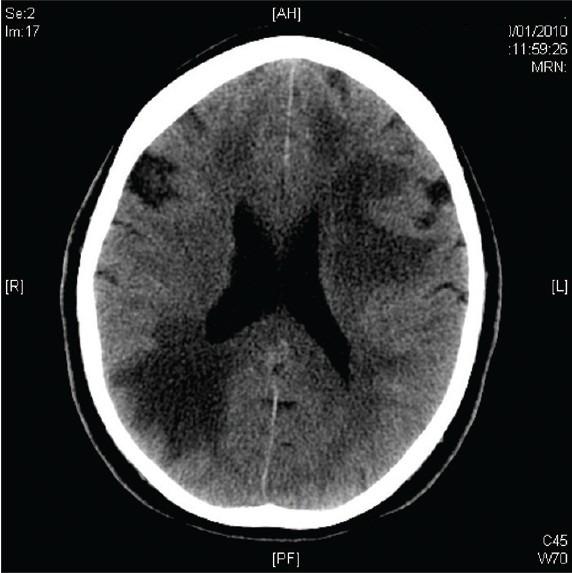

一例发生于脑部的大B细胞血管内淋巴瘤。

A case of large B-cell intravascular lymphoma in the brain.

Intravascular lymphoma is a rare and fatal disease that can have central nervous system (CNS) manifestations. It is usually a diagnosis made postmortem. This is partly due to its varied presentation, which lends itself to the complexity of diagnosis.

We report a rare case of intravascular lymphoma in the brain found antemortem.